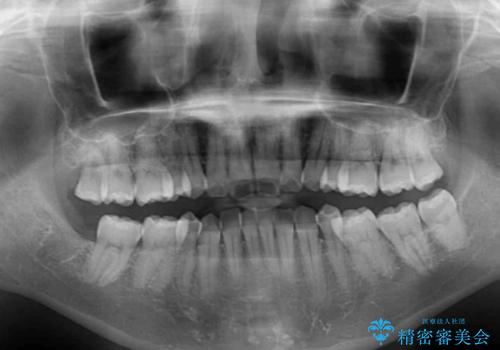

- 以前矯正治療をされていましたが、後戻りが起きたことを気にして来院された患者様です。

全顎的に認められた叢生を改善するため、インビザラインにて治療を行うこととしました。

前歯の叢生の改善を目的として、IPR(歯と歯の間を削る)と歯列全体の後方移動によって歯並びを整えることとしました。

臼歯部も含め、叢生が綺麗に改善され、患者様には大変満足していただきました。